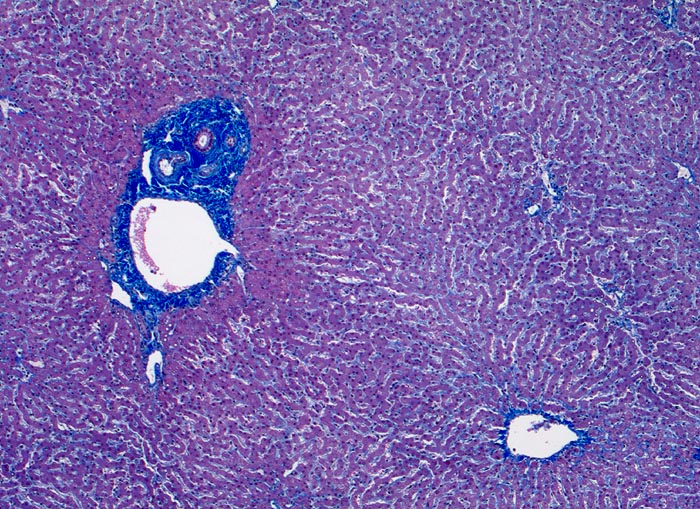

PathoPic – image database / PathoPic ID 3124 - Normales Leberparenchym mit Portalfeld und Zentralvene

Normales Leberparenchym mit Portalfeld und Zentralvene

Links im Bild ein Portalfeld mit Portalvenenast, Arterienast und Gallengang. Das Portalfeld zeigt eine minimale Fibrose. Keine Entzündugnsinfiltrate. Rechts unten im Bild ein Zentralvenenast. Das Parenchym zeigt keine Verfettung und keine Entzündungsinfiltrate. Die Sinusoide sind nicht dilatiert.

Vergrösserung

50